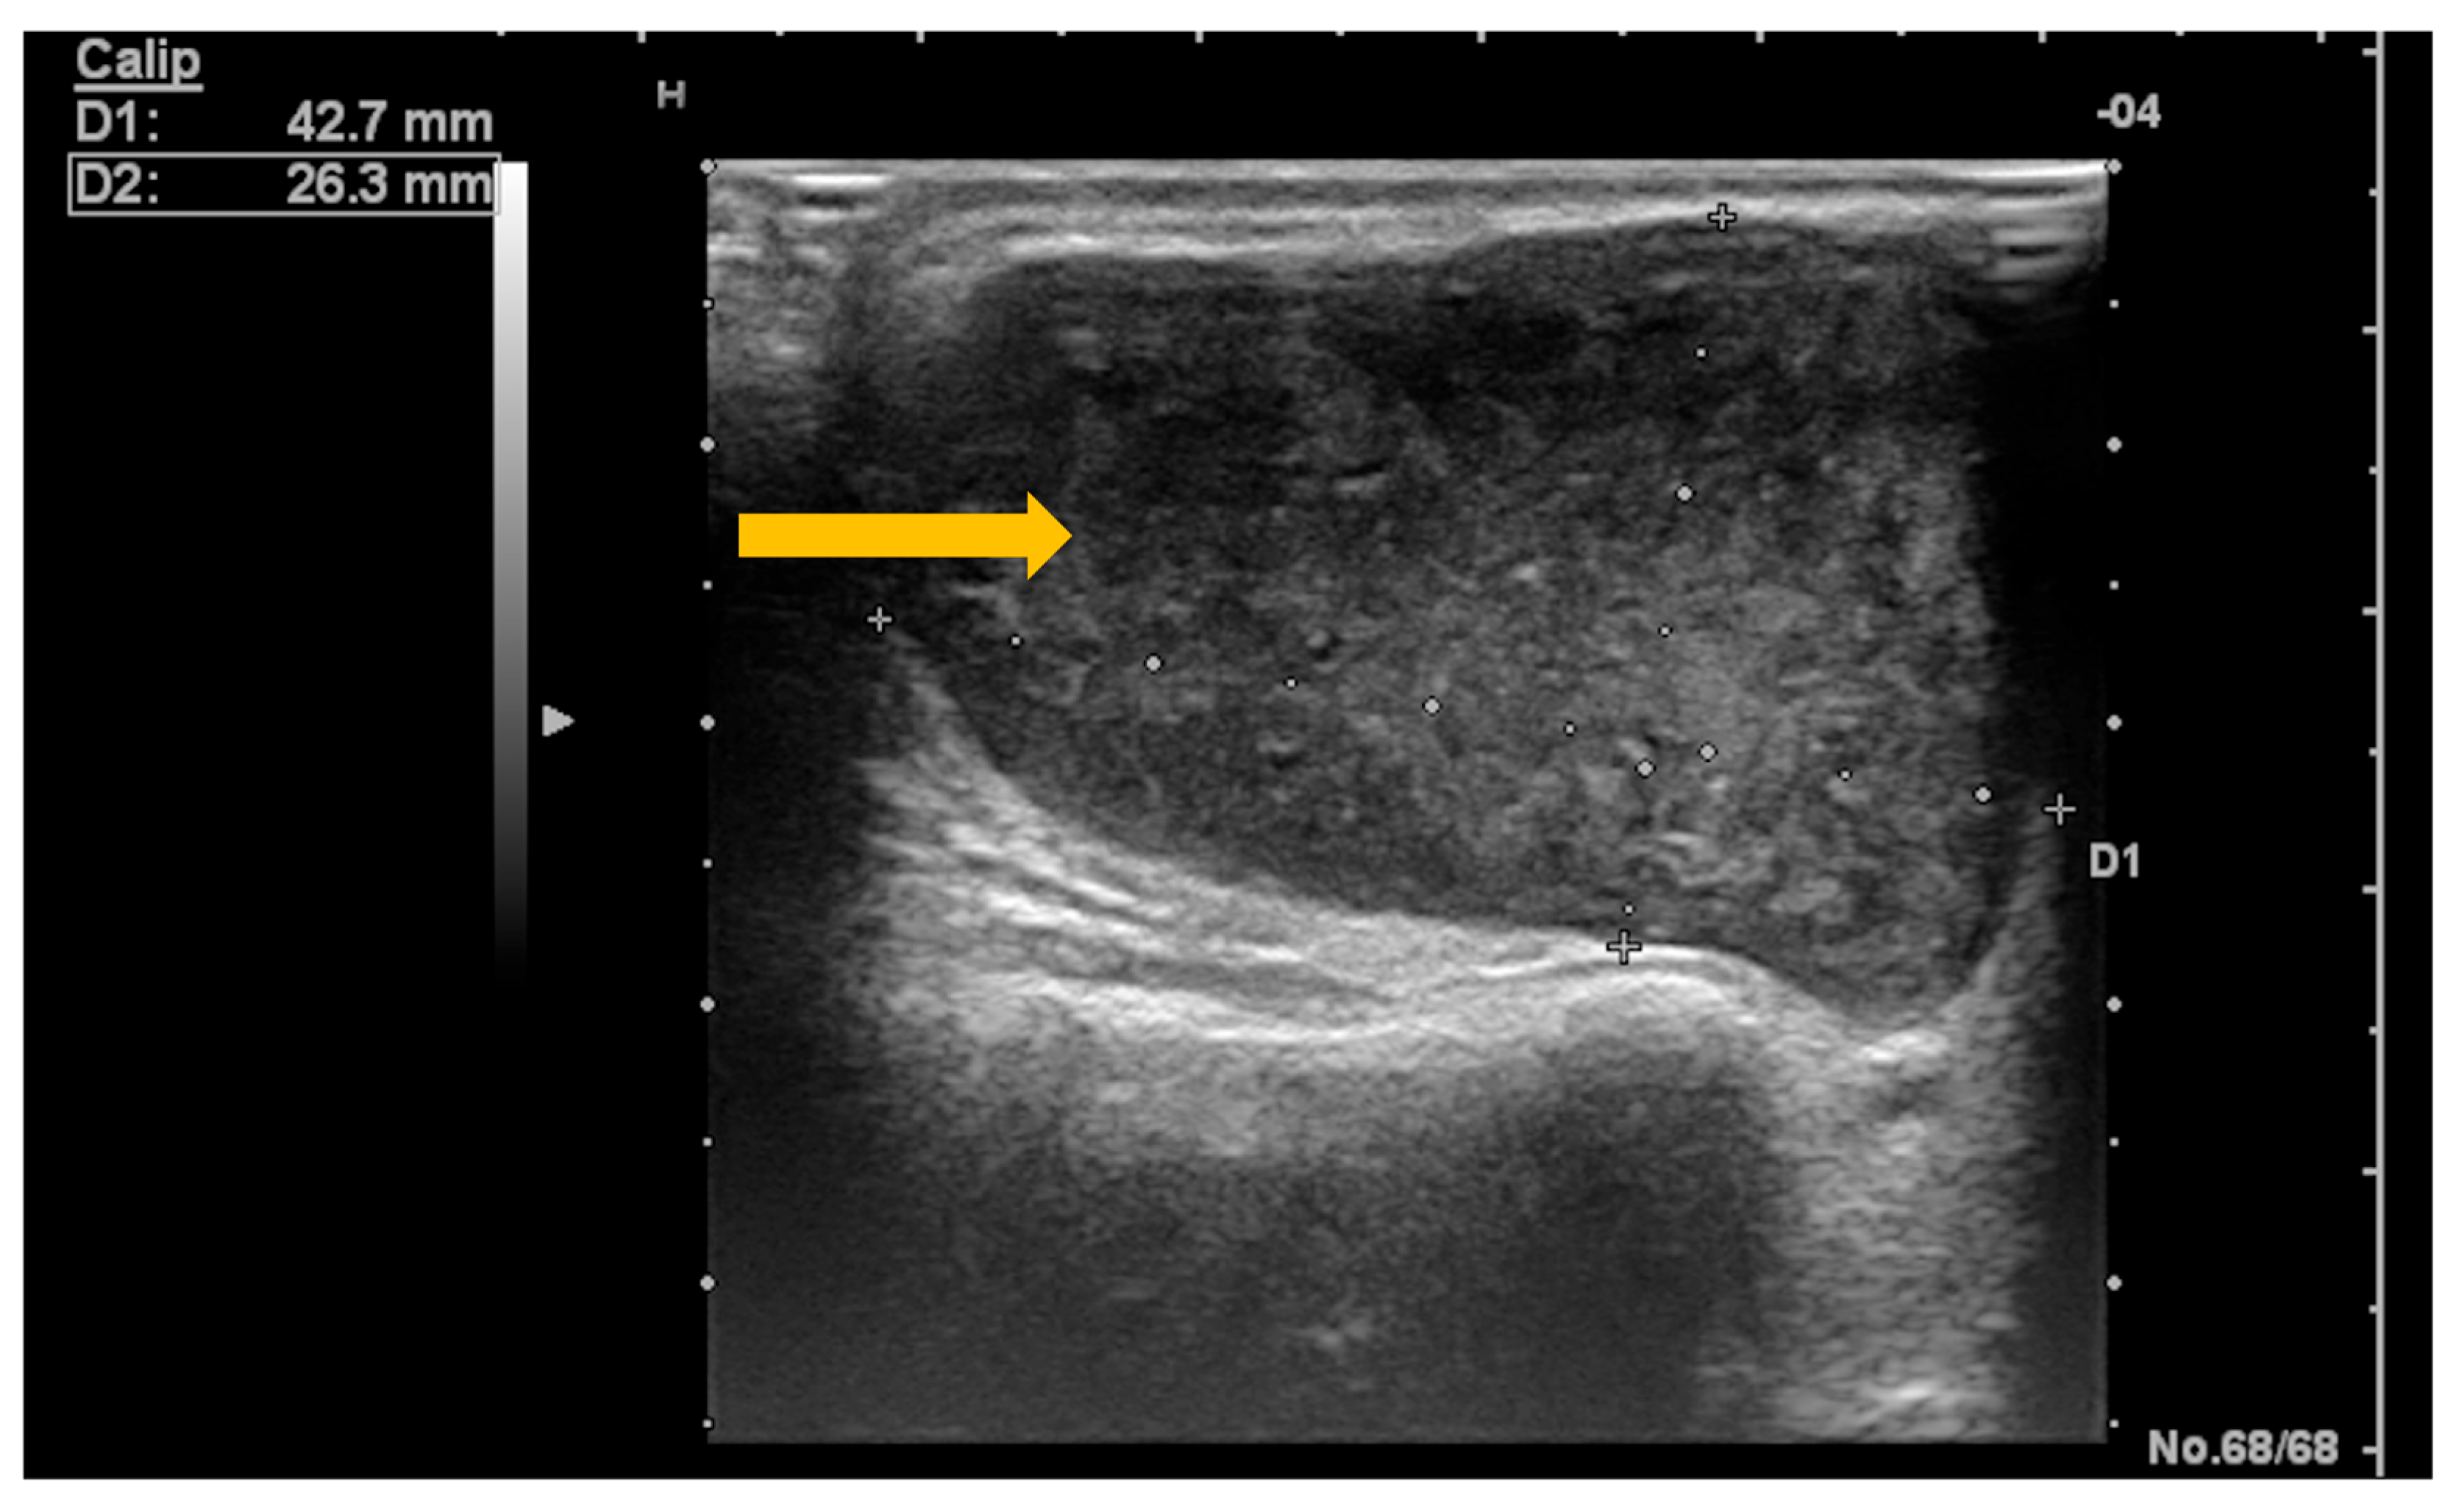

Ultrasonography is the imaging tool most frequently used in clinical practice due to its non-invasive nature, low cost, and wide availability [64]. Dynamic ultrasonographic evaluation of the salivary glands can identify a newly developed hypervascular, oval, relatively well-defined, hypoechoic nodular lesion with intrinsic hyperechoic septa and posterior acoustic enhancement (Figure 8 and Figure 9) [64,65]. At the same time, ultrasonography can be used to guide biopsies of lesions with suspicious imaging characteristics [63].

Figure 8. B-mode ultrasound of the parotid gland in a patient with Sjögren’s syndrome. Gray-scale (B-mode) ultrasound demonstrates a newly developed hypoechoic nodular lesion within the parotid gland (arrow), a finding suspicious for salivary gland lymphoma in the clinical context of Sjögren’s syndrome.